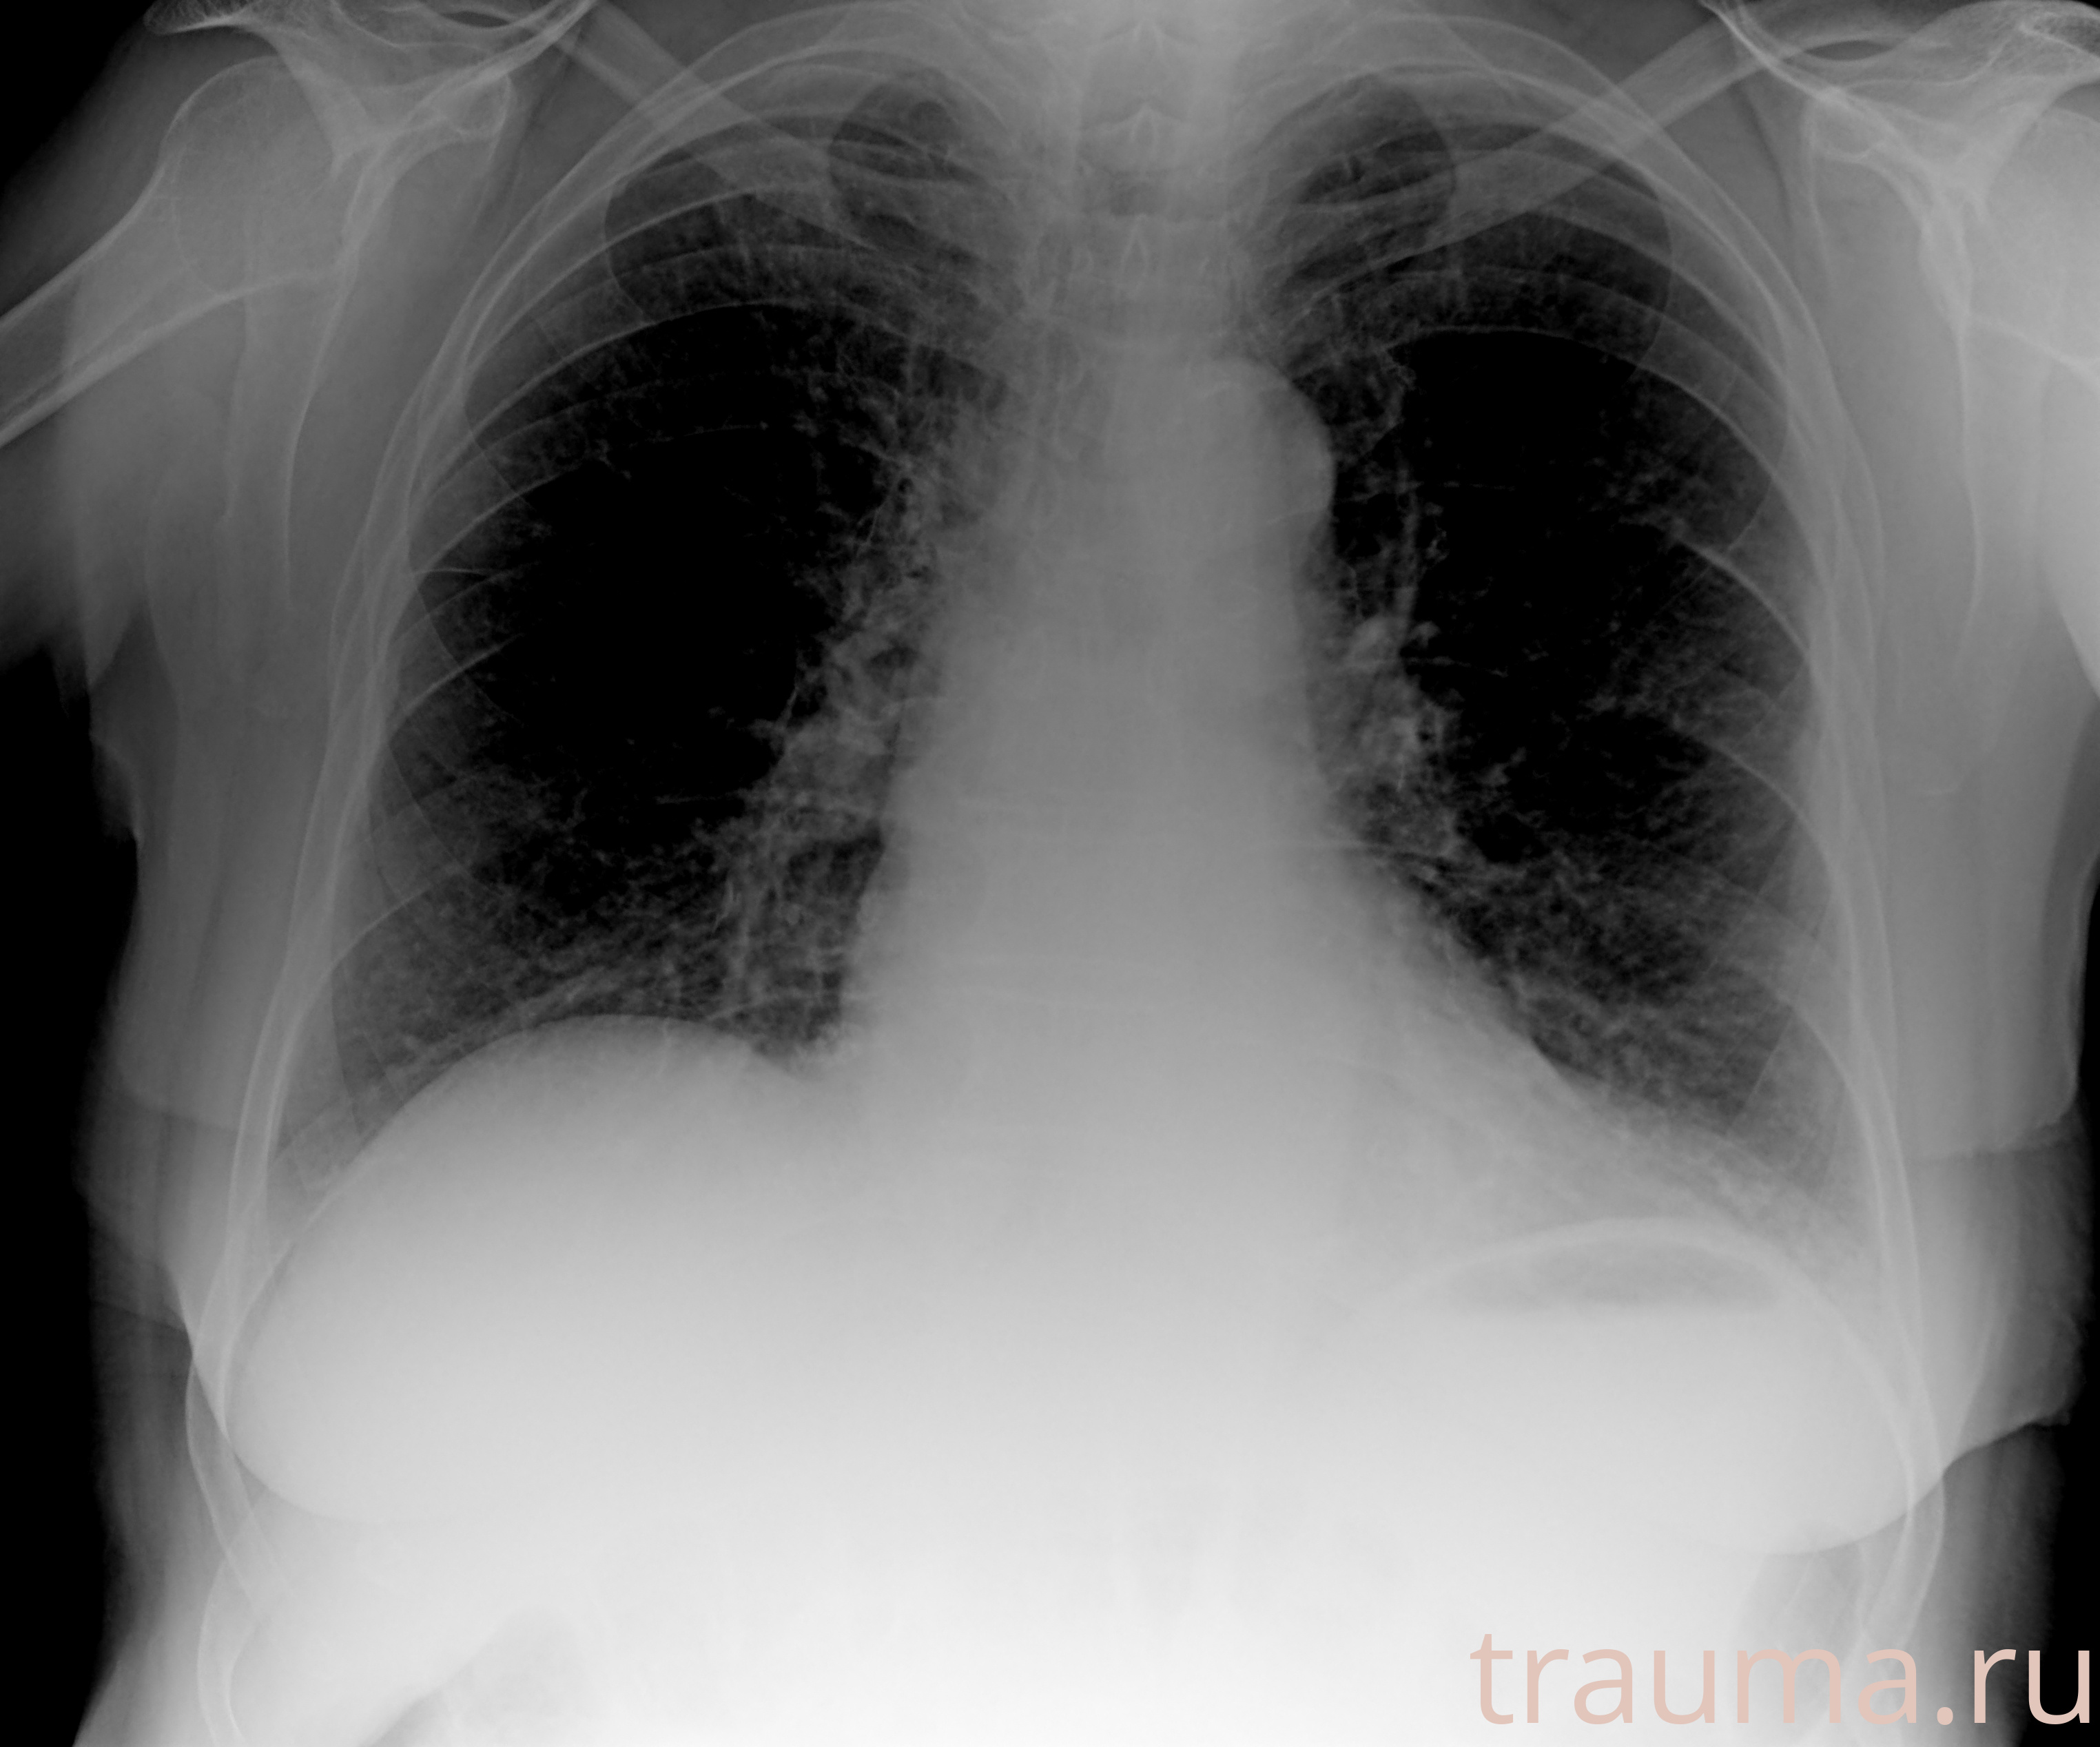

Рентгенограммы

Рентген на дому: по вашему адресу приезжает врач-рентгенолог, травматолог-ортопед с мобильным рентгеновским аппаратом, проводит диагностику травмы или заболевания, делает необходимые рентгенограммы, дает рекомендации по дальнейшему лечению. Получить качественные снимки в домашних условиях возможно благодаря уникальной методике, разработанной МосРентген Центром для института  Склифосовского

при переломе шейки бедра и пневмонии от компании МосРентген Центр - партнера Института имени Склифосовского